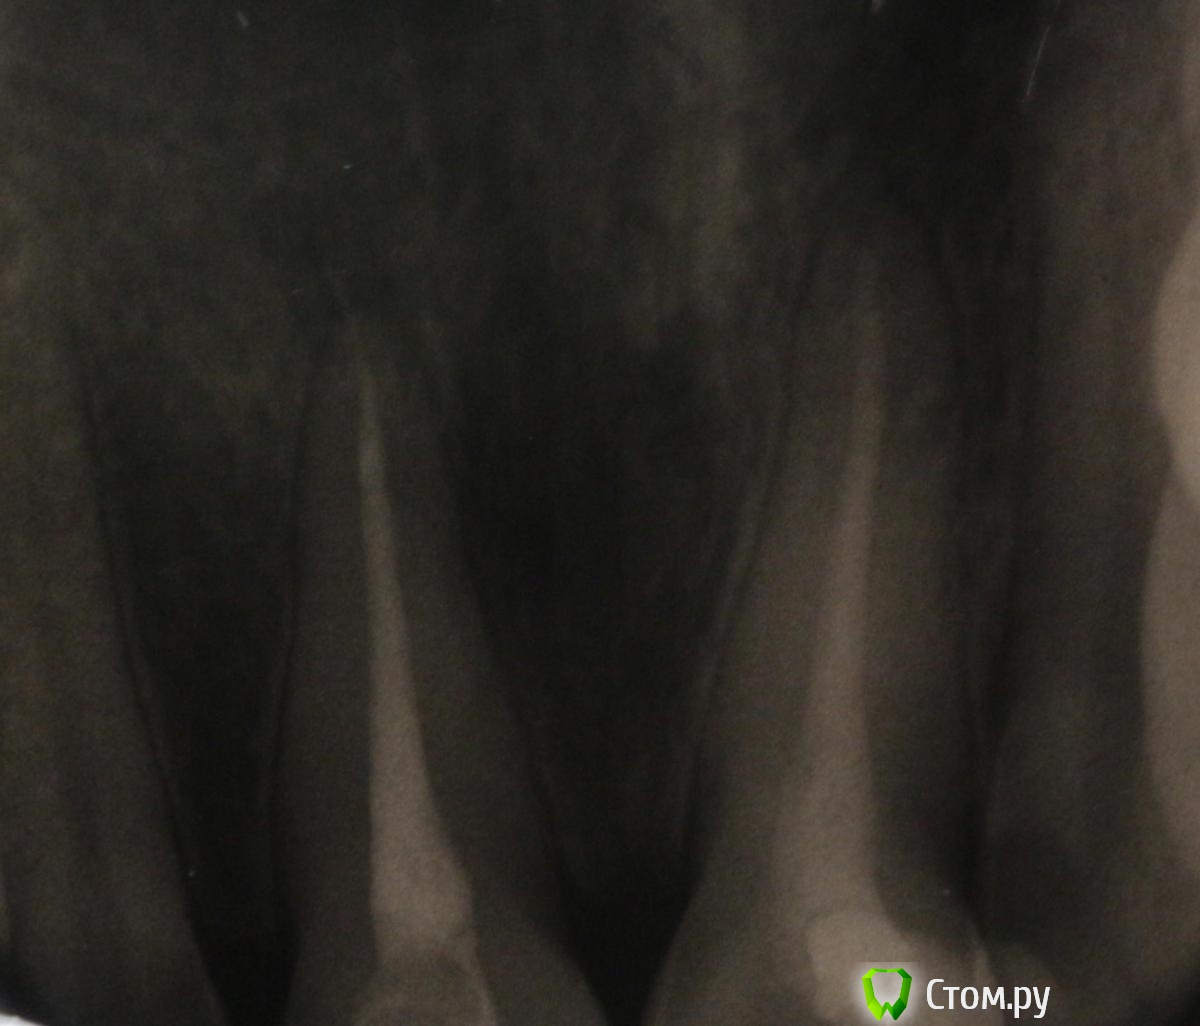

bmr Опубликовано 19 января, 2014 Поделиться Опубликовано 19 января, 2014 Здравствуйте. Такая проблема. Пролечили зуб. Врач поставил диагноз - пульпит. Прошел месяц после лечения. Первые 10 дней зуб болел сильно. Потом боль начала стихать. Теперь она еле заметная. Возникает при нажатии на зуб пальцем с внешней стороны. При накусывании боли как таковой нет. Сделали гентген. Врач сказал, что вывел гуттаперчу, чтобы не образовалась киста. Сказал, что перелечивать не нужно, само пройдет. Сказал, что требуется полоскать водой с содой. Проверье, пожалуйста, правильные ли выводы сделал врач. Не хочется терять передний зуб.До леченияПосле Ссылка на комментарий

bmr Опубликовано 20 января, 2014 Автор Поделиться Опубликовано 20 января, 2014 Почему? Не знаю, видно ли это на фото, но на снимке отчетливо видно потемнение вокруг выведенной гуттаперчи. Врач сказал, что это гнойный мешочек и он рассосется сам. Организм справится. Возможно ли это? Ссылка на комментарий

anvladd Опубликовано 20 января, 2014 Поделиться Опубликовано 20 января, 2014 потому что апикальная треть корня обработана(запломбирована) не очень хорошо и это видно на снимке. Гуттаперчу выводить нельзя,пломбировочный материал(силер) бывает "выплевывает" за верхушку,что тоже не желательно,но не критично.дай бог чтобы организм справился,но я бы переделал. Ссылка на комментарий